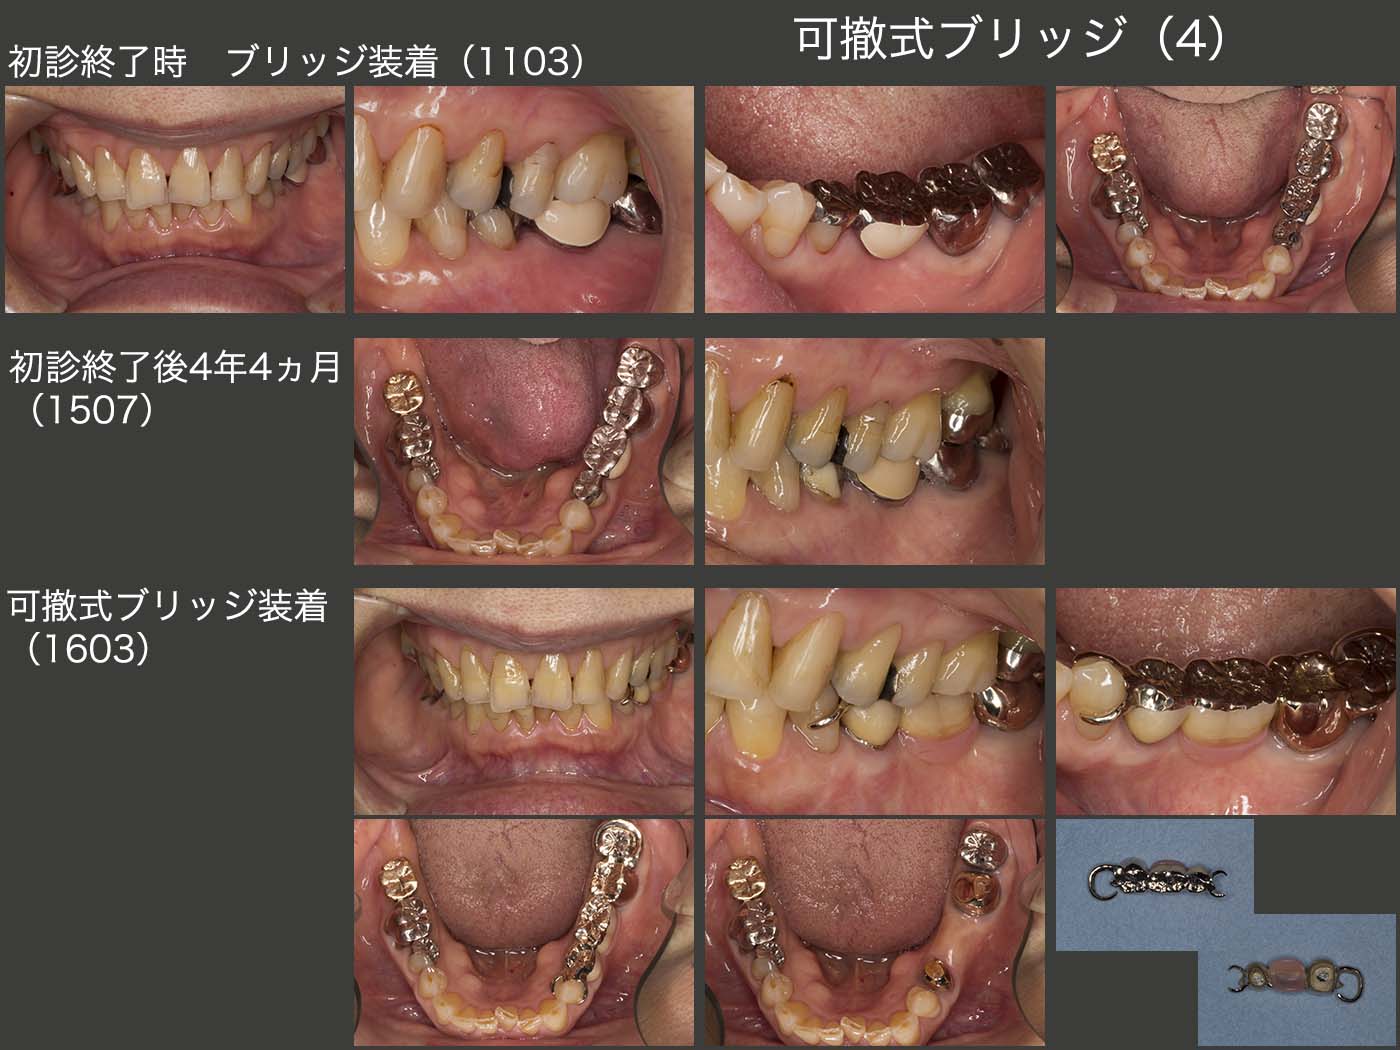

4.症例4

2008年初診,60歳女性.10年12月に左下ブリッジが脱落したとのことで,11年3月に新たにブリッジを製作した.なお,旧ブリッジは4年前に他院にて製作したとのこと.咬合力が明らかに強そうであり,またすぐに脱落する可能性が高いことから,可撤式のブリッジ(コーヌス義歯)を勧めたが,患者さんの了解を得ることはできなかった.ブリッジの片側脱離を危惧し,ブリッジを仮着して経過をみることにした.

スライドにはないが,12年11月に左下5の片側脱離が生じ,う蝕が歯髄まで進行していたため,抜髄する羽目になってしまった.何のための仮着であったのか?そして,今度はブリッジを本止めした.

しかし,15年7月に再び左下5の片側脱離が生じた.11年の時に,左下5の頰側を金属でさらに覆い,本止めしておけばブリッジの寿命はもっと長くなったはずである.しかし,いずれ片側脱離が生じることは間違いないと思われる.咬合力の強さ,右下7にインプラントが装着されているが,主咀嚼側は左側であること等,この症例には固定式ブリッジが適応しないと思われる.

少なくとも5年前に可撤式ブリッジにしておけば,左下5の抜髄は避けられた.また左下5および7は無髄歯であるから,将来歯根破折が生じる可能性が高い.そこで,左下4および8にクラスプをかけ,水平的な力を少し担ってもらうと同時に,左下5および7に最悪歯根破折が生じても,マイナーチェンジで対応できるような設計を行った.(16年3月)

20年10月,特に問題なく経過している.